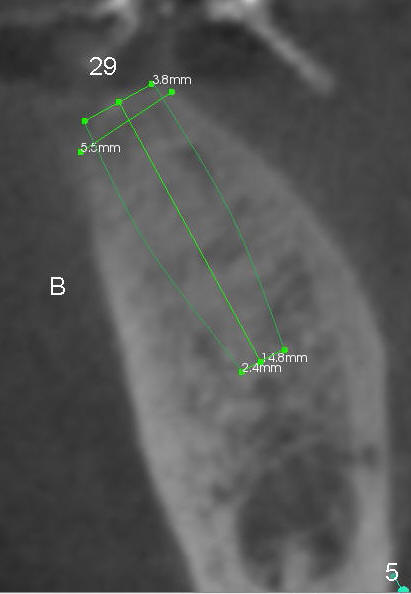

A 85-year-old man has poor dentition (Fig.9). Multiple implants are to be placed at one or two stages (#26-30). If primary stability is obtained for individual implants, they are splinted and immediate provisional is fabricated.

Fig.1-3 are CBCT sagittal sections of the lower right quadrant, whereas Fig.4-8 are coronal sections. The lower left quadrant has been restored.